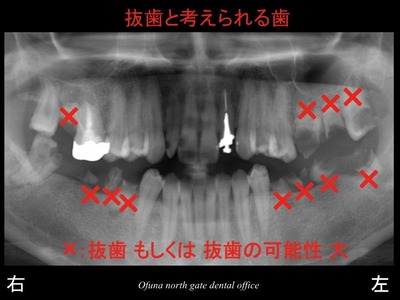

以下は初診時のレントゲンです。

いつも見ている方には みなれたことと思います。

始めて見られる方のために 簡単に以下のレントゲンの見方

について説明します。

以下のレントゲンの下に 右、左と書いてありますが、

当然のことながら 右と書いてあるのが“ 右側 ”です。

実際の左右とは違いますので、今後見られる時にはご注意下さい。

虫歯がいっぱいあることが分かるかと思います。

このように多くの虫歯がある方がいらっしゃいます。

多くの歯が抜歯となるような状態です。

また、以下の歯も抜歯ではありませんが、将来性は低い歯と言えます。

本当に多くの歯に問題があります。

先程の×印を抜歯した場合には、以下の2つの治療方法が考えられます。

まず、以下の×印のみを抜歯します。

これらの歯はどうしても残す(保存する)ことは不可能だからです。